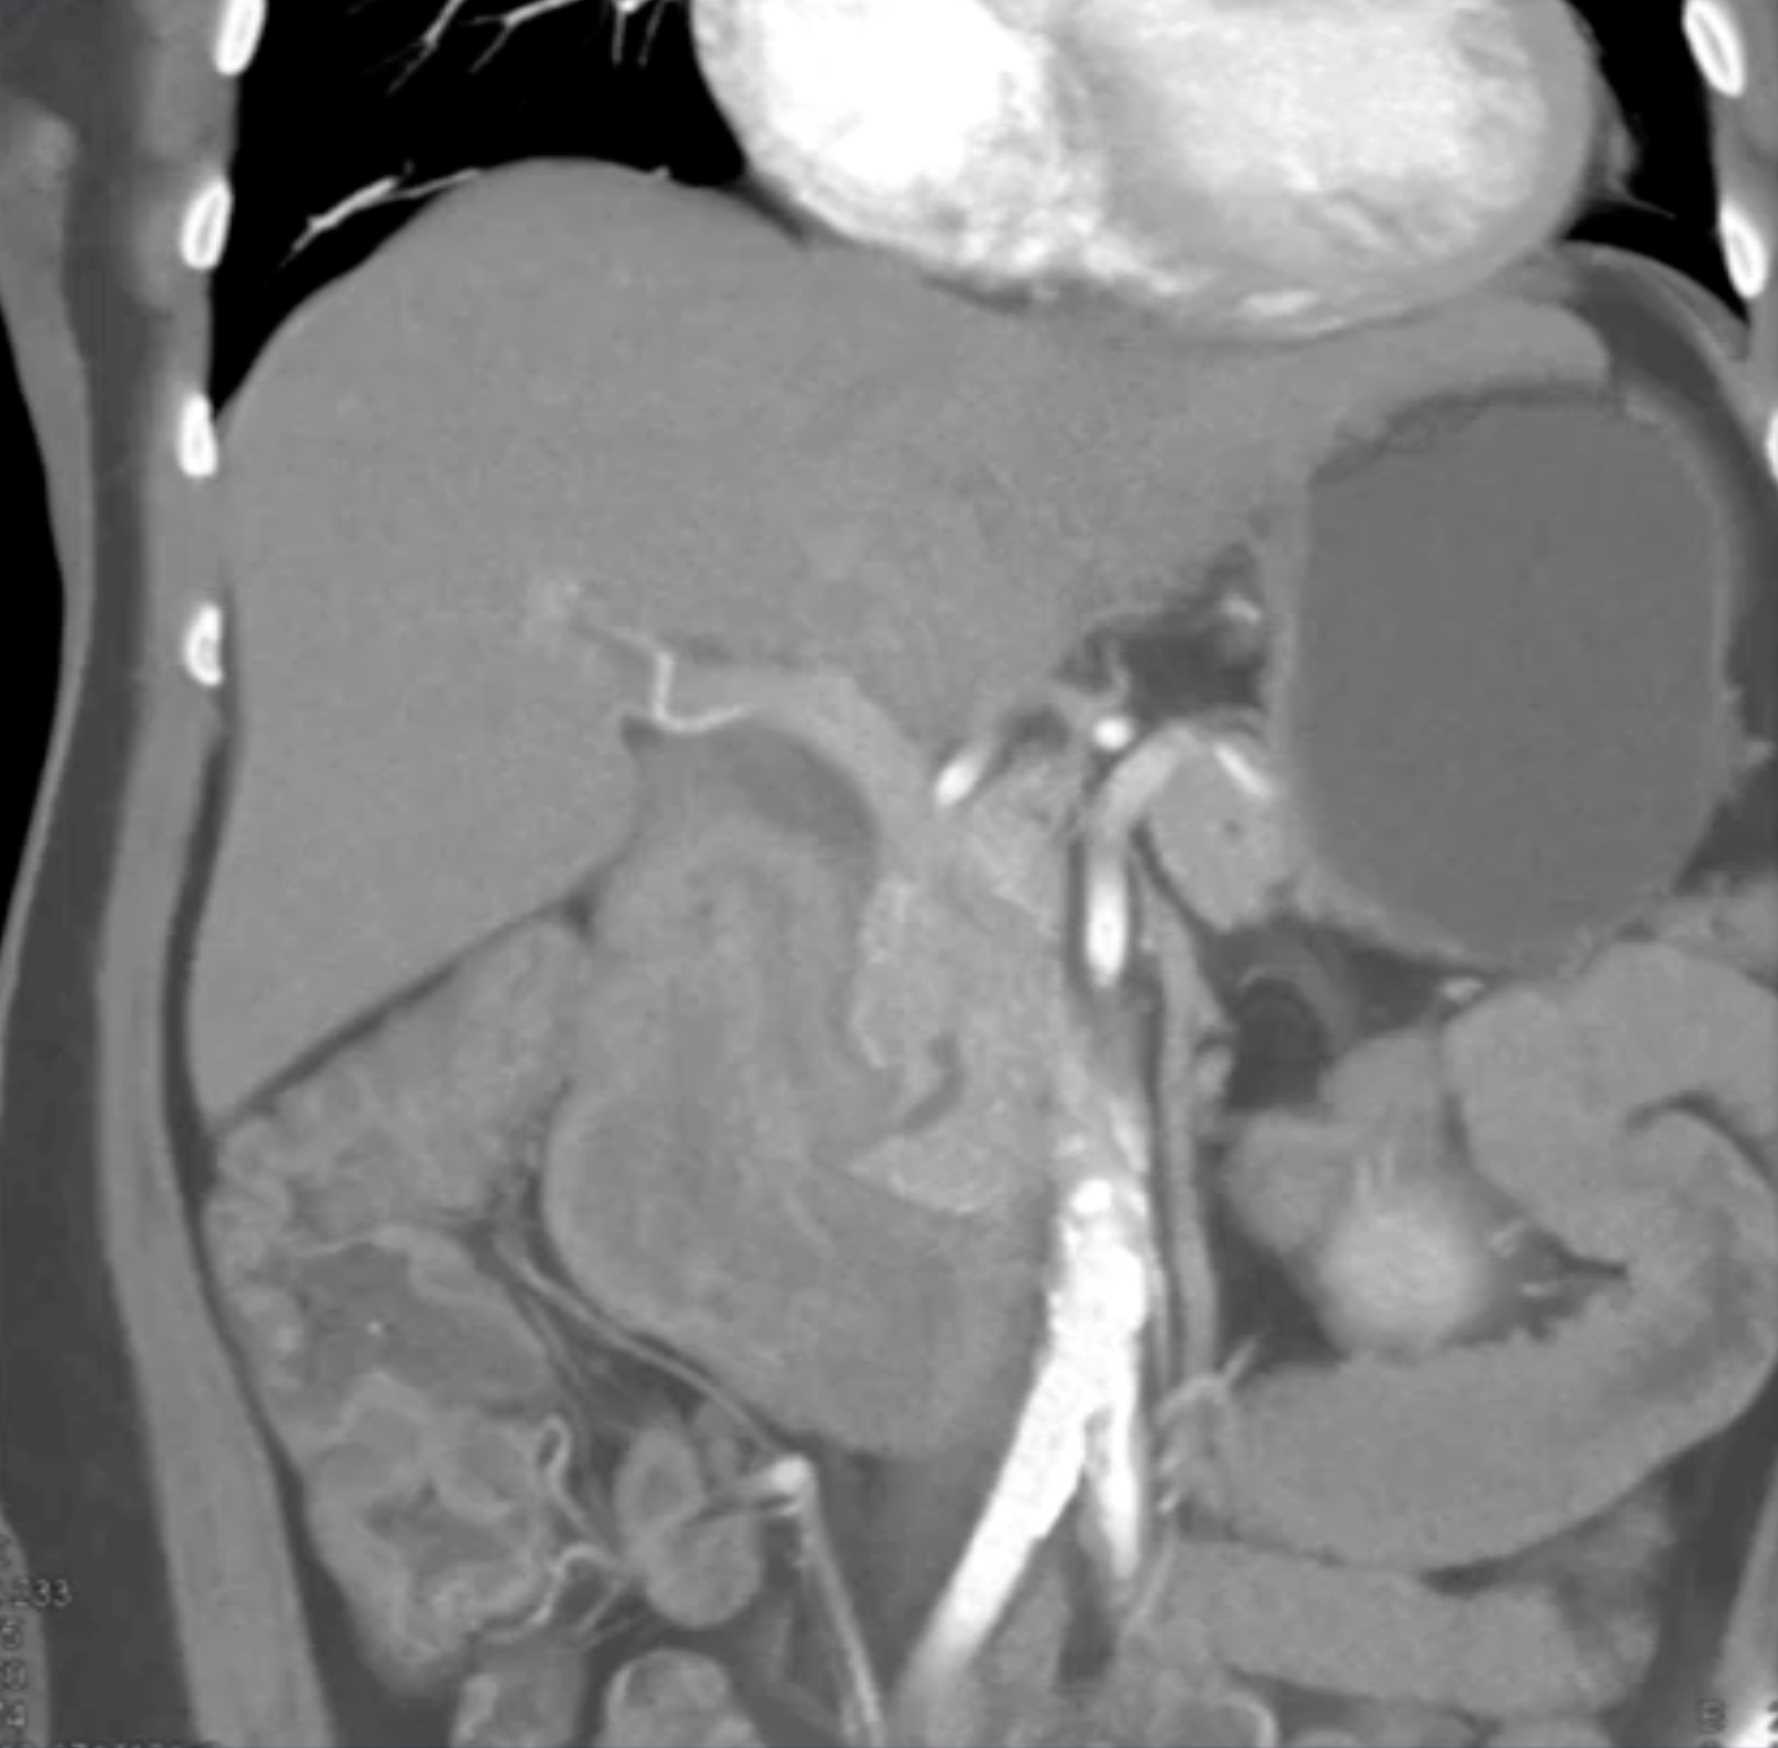

Lagre Gastric GIST Tumor